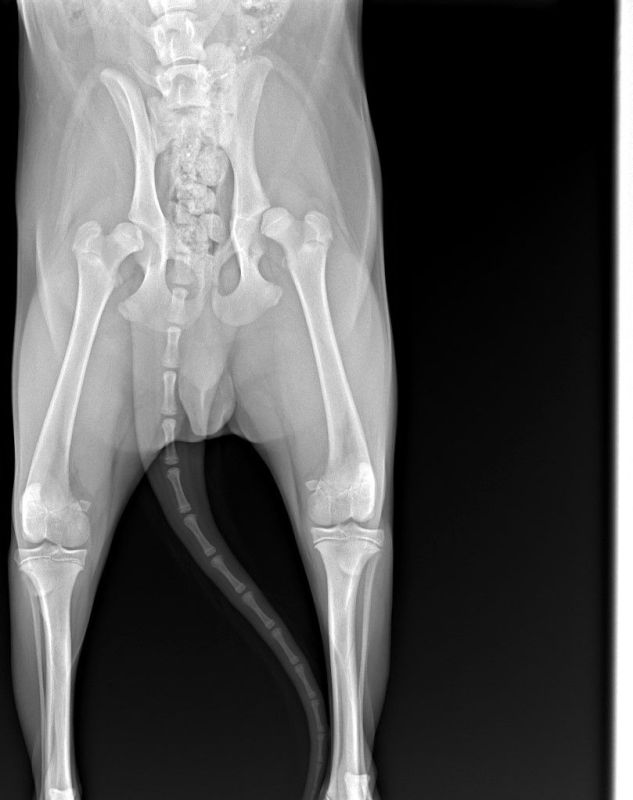

Оборудование для диагностики высокой точности

Какие патологии мы лечим